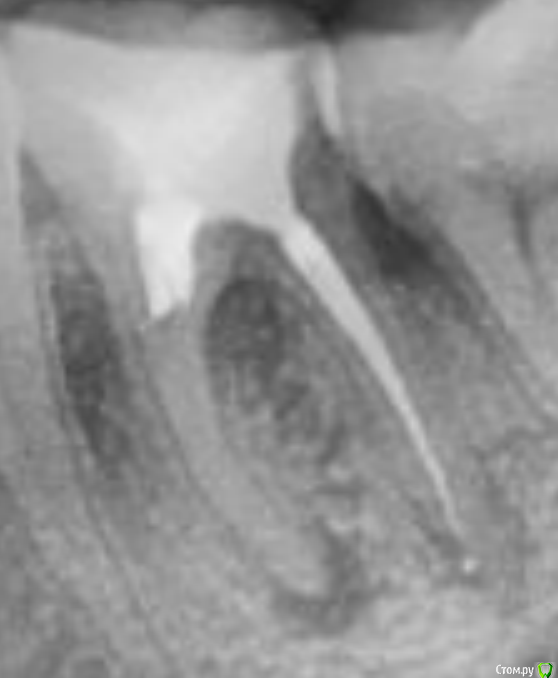

4. 3 года назад пошёл к новому враче лечить остальные зубы, и заодно решил перелечивать этот. Врач делал снимок прицельный сказал, что у корня есть воспаление, он заложит лекарство и запломбирует канал. Вот сам снимок зуба.

При попытке пройти второй канал, в которым якобы был сломанный инструмент. Врач сказал, что никакого инструмента там нету. Но канал настолько сросся, что пройти его нет возможности. В итоге насколько возможно было запломбировали.